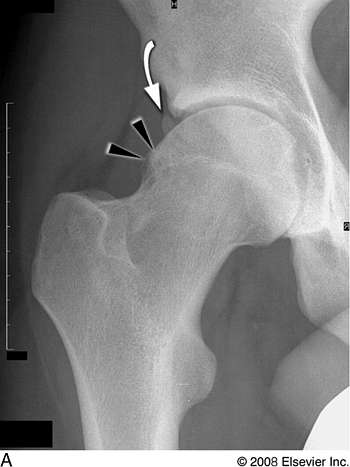

X-Ray

If your clinician suspects femoroacetabular impingement, you may be referred for an x-ray.

This is used to assess the bone and joint structure of the pelvis and proximal femur, and is capable of assessing the shape of the bones of the hip joint as well as the quality of the joint space and presence of degenerative changes in the hip.

However, an X-ray does not show the soft tissues such as the labrum, articular cartilage and tendons which can also be problematic in FAI.